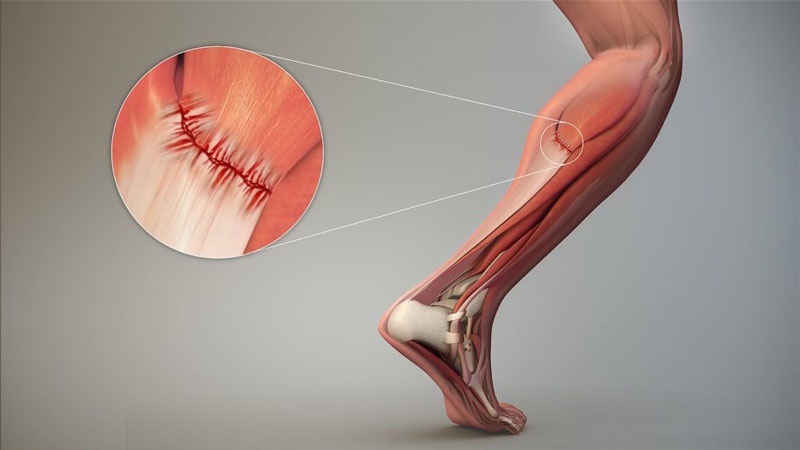

Rách cơ đùi sau, cơ bắp chân

Xuất hiện trong các môn cần tăng tốc mạnh. Triệu chứng: đau nhói tức thì, căng cứng và giảm lực cơ rõ rệt.